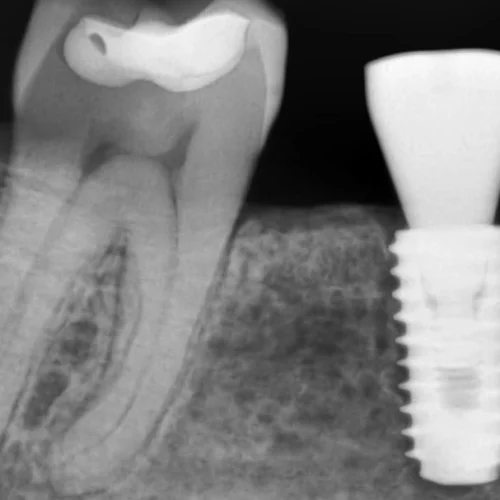

Medical illustration of temporomandibular joint (TMJ) showing jawbone, muscles, and joint structure in a woman’s face

The temporomandibular joint (TMJ) connects the jaw to the skull and plays a key role in chewing and speaking. Disorders of this joint can cause pain, stiffness, and difficulty in movement.

• Imaging Tests: X-rays, panoramic radiographs, or CBCT scans for detailed joint evaluation